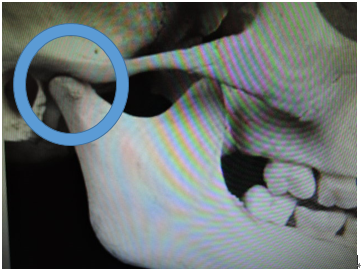

全ての歯が萌え揃うと顎の関節は写真の様に骨で固まってしまいます。

この為、下顎骨が後ろに後退し生じた出っ歯などは非抜歯での治療が難しくなります。

このため下顎骨が後ろに後退したために生じた出っ歯などは、非抜歯での治療が難しくなります。